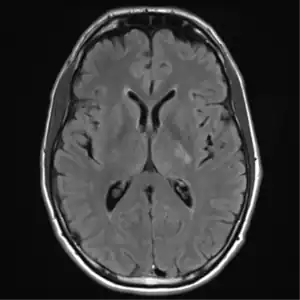

text: From left to right: Cryptococcosis lung, cryptococcosis brain | |

Brain

Cryptococcal meningitis (infection of the meninges, the tissue covering the brain) is believed to result from dissemination of the fungus from either an observed or unappreciated pulmonary infection. Often there is also silent dissemination throughout the brain when meningitis is present. Cryptococcus gattii causes infections in immunocompetent people (fully functioning immune system), but C. neoformans v. grubii, and v. neoformans usually only cause clinically evident infections in persons with some form of defect in their immune systems (immunocompromised persons). People with defects in their cell-mediated immunity, for example, people with AIDS, are especially susceptible to disseminated cryptococcosis. Cryptococcosis is often fatal, even if treated.[19]

Though the rate of infection is clearly higher with immunocompromised individuals, some studies suggest a higher mortality rate in patients with non-HIV cryptococcal meningitis secondary to the role of T-cell mediated reaction and injury.[20] CD4+ T cells have proven roles in the defense against Cryptococcus, but it can also contribute to clinical deterioration due its inflammatory response.[21]

CT scan lungs: mass in right upper lobe MRI brain: cryptococcus

The immune reconstitution inflammatory syndrome (IRIS) has been described in those with normal immune function with meningitis caused by C. gattii and C. grubii. Several weeks or even months into appropriate treatment, there can be deterioration with worsening meningitis symptoms and progression or development of new neurological symptoms. IRIS is however much more common in those with poor immune function (≈25% vs. ≈8%).Magnetic resonance imaging shows increase in the size of brain lesions, and CSF abnormalities (white cell count, protein, glucose) increase. Radiographic appearance of cryptococcal IRIS brain lesions can mimic that of toxoplasmosis with ring enhancing lesions on head computed tomography (CT). CSF culture is sterile, and there is no increase in CSF cryptococcal antigen titre.